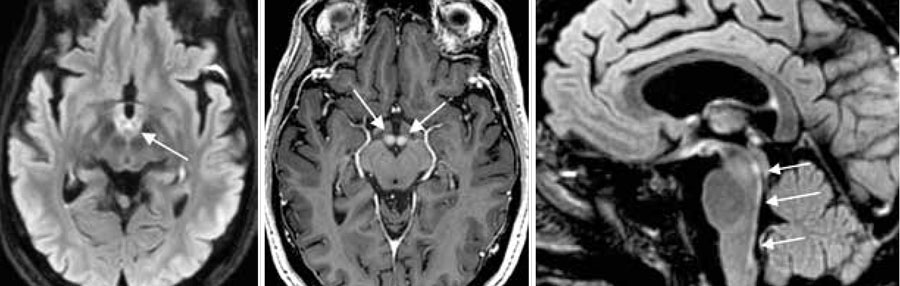

En MR-undersökning med kontrast av hjärnan visade på FLAIR (fluid attenuated inversion recovery)-­sekvensbilder patologiskt hög signal subependymalt inferiort i tredje ventrikeln, i akvedukten och i mediala hypotalamus bilateralt (Figur 1). Vestibulärt impuls­test med videoinspelning (vHIT) (Synapsys, Marseille) dagen efter inläggning visade selektivt bilateralt bortfall av horisontell vestibulo-okulär reflex (Figur 2).

Figur 1. MR-hjärna från mannen i fall 1. Till vänster: FLAIR-sekvens med patologisk signalintensitet subepen­dymalt kring tredje ventrikeln inklusive adhaesio interthalamica. Mitten: FLAIR-sekvens med ett tunt lager högsignalerande vävnad kring akvedukten och fjärde ventrikeln. Till höger: T2-viktad bild med ökad signal­intensitet i den pontomedullära kopplingen, posteriort i hjärnstammen på platsen för de mediala vestibulariskärnorna.

Figur 3. MR-hjärna från mannen i fall 2. Till vänster: FLAIR-sekvens med bilateralt patologisk signalintensitet i mamillarkropparna (minnesstörning). Mitten: T1-viktad bild med kontrast som visar bilateral kraftig kontrastladdning i mamillarkropparna (minnesstörning). Till höger: FLAIR-sekvens med patologisk signalintensitet i bakre kanten av hjärnstammen (nystagmus, abducenspares, bortfall av horisontell vestibulo-okulär reflex).